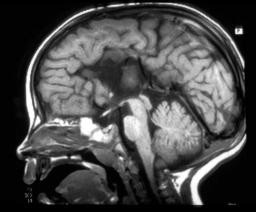

Agnese van het corpus callosum

afwijking ten gevolge van migratie